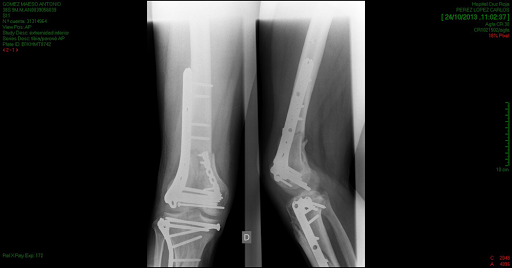

Maeso, madrileno classe 1979, è stato infatti vittima di un bruttissimo incidente durante la Superbike Race al TT 2013. Una gamba distrutta, un’operazione durata 12 ore e l’amputazione evitata solo dopo aver scongiurato i medici dell’ospedale di Liverpool, proprio come fece Ian Hutchinson. Un incidente, tuttavia, passato piuttosto in sordina.